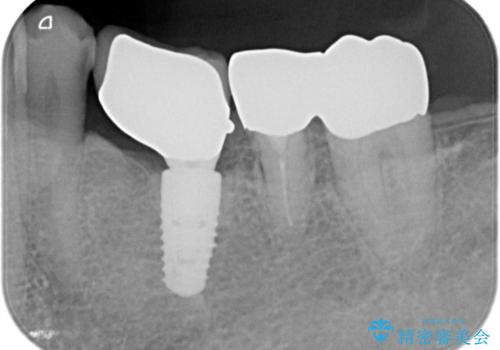

- 「歯を咬むと痛い」を主訴に来院された患者様です。 CTを撮ると歯根が縦に真っ二つに割れている状態で、歯周ポケットも10㎜を超える状態でした。

歯の保存は困難と診断しインプラントで治療を行いました。1Dayインプラントの適応だったので、抜歯した当日にインプラントを埋入しました。

1Dayインプラントは低侵襲なので痛みもほとんどありません。従来のインプラント治療だと1年弱かかるのが、3ヵ月で治療を終える事が出来ました。